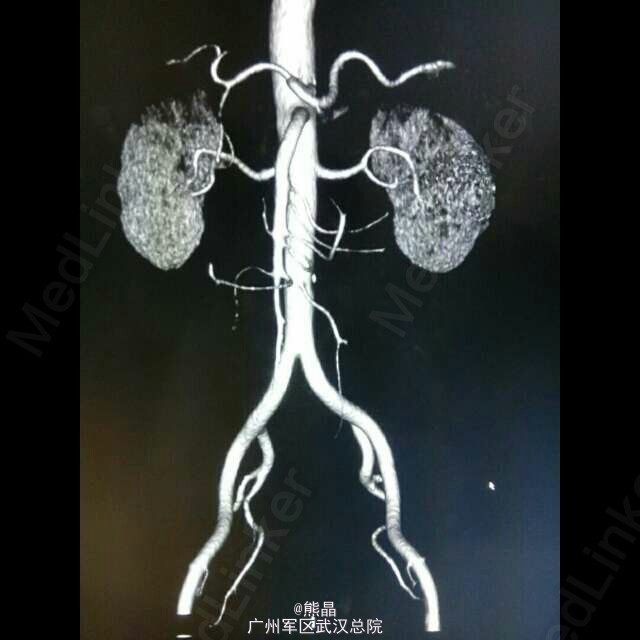

患者男性,61岁,体检发现左肾占位病变5天,无明显临床症状。 肾脏嗜酸性细胞瘤是一种少见的肾脏良性肿瘤,与肾癌鉴别较困难。 肾脏嗜酸性细胞瘤增强扫描可以出现轮辐状强化,是其特征之一,肿瘤中可见星状瘢痕,为纤维母细胞增生,如肿瘤中有钙化,可以除外嗜酸。